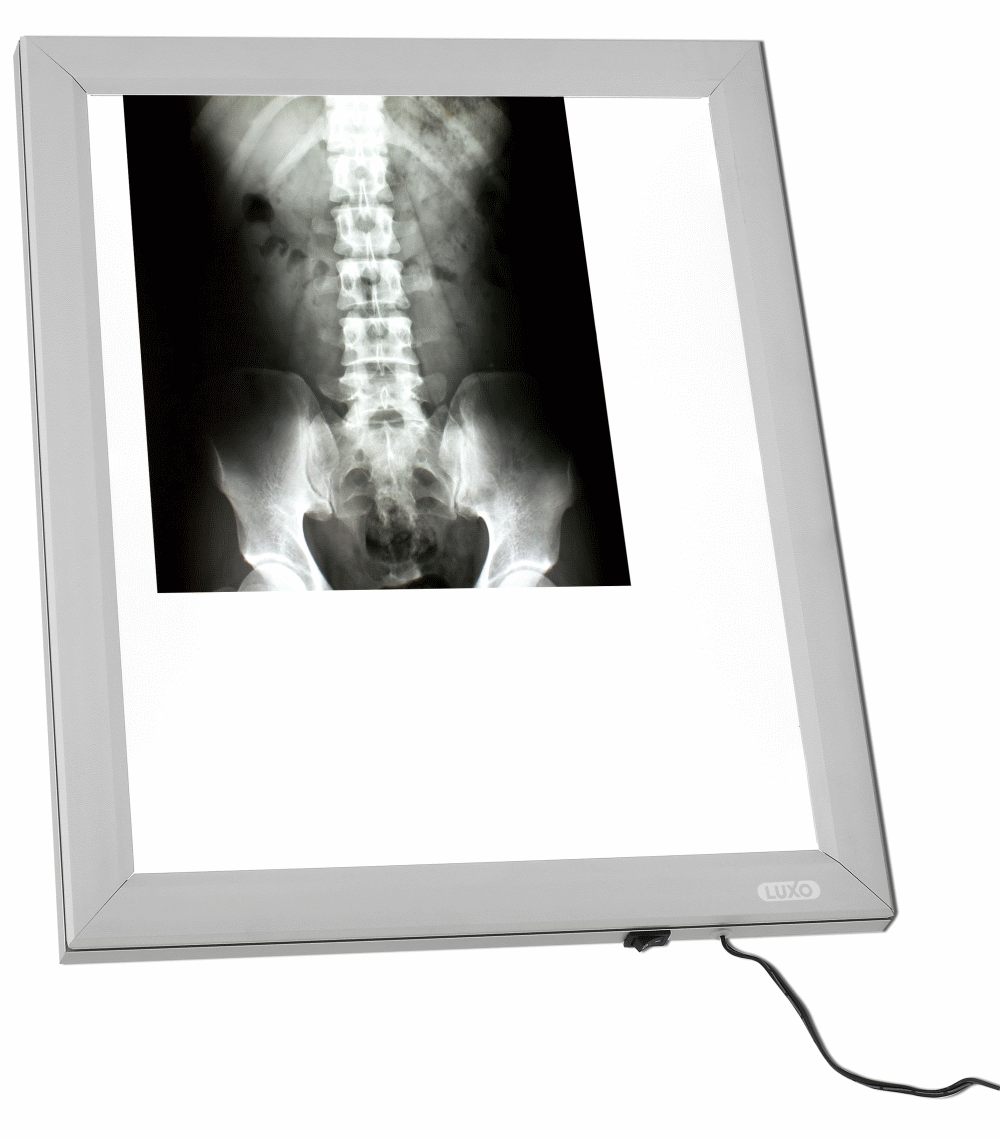

Организация рабочего пространства: стенды для рентгеновских снимков